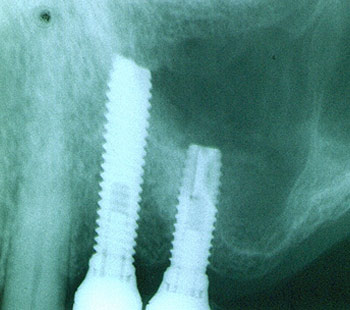

Voraussetzung für das Einbringen und eine lange Verweildauer eines Implantates ist ausreichend vorhandener Knochen. Abhilfe kann vielfach durch Knochenaufbauten geschaffen werden. Nebenstehendes Bild zeigt die zusätzliche Verknöcherung von Kieferhöhlenarealen, um ausreichenden Halt für die zwei Implantate zu schaffen.